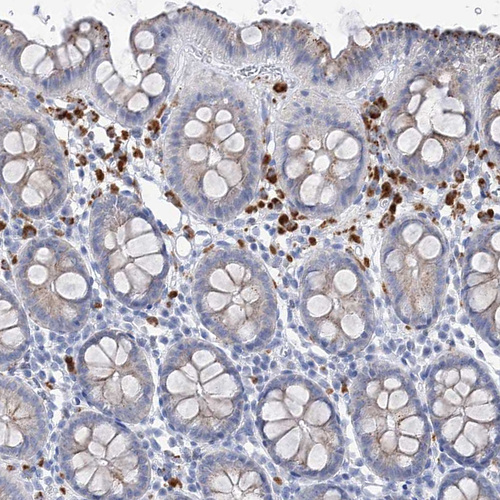

Immunohistochemical staining of human cerebellum shows strong cytoplasmic positivity in Purkinje cells.